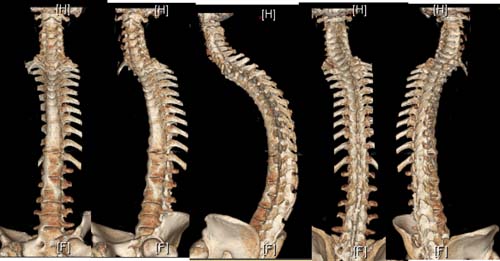

术前大体像

术前影像图像